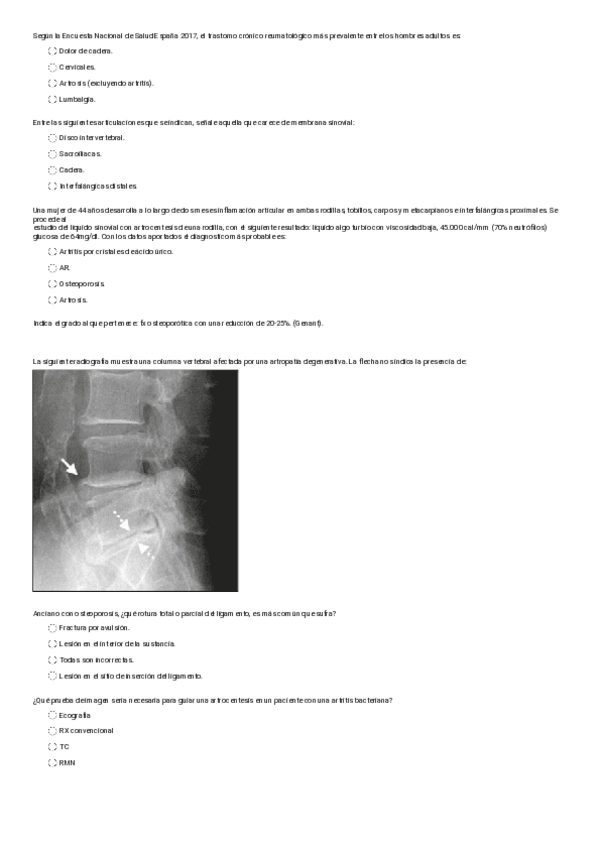

Exámenes - Test-osteo-reuma.pdf